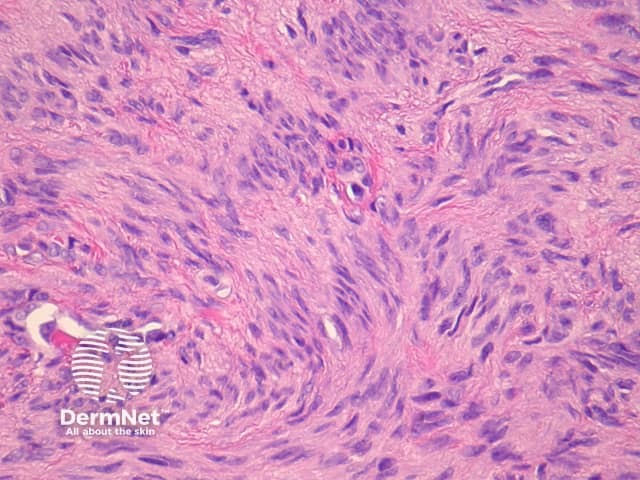

Compared with usual dermatofibroma, cellular dermatofibroma has an increased chance of recurrence following excision and metastasis is reported. Histologically, there is increased cellularity with a swirling, storiform pattern (figures 3,4). Peripheral entrapment of collagen is less prominent in this variant. There may be increased mitoses and extension to the subcutaneous fat, which are associated with more aggressive behaviour. Approximately 10% of cases show central necrosis.

Cellular dermatofibroma may resemble dermatofibrosarcoma protuberans, which can be differentiated by its larger size, increased mitoses and marked involvement of the subcutis. CD34 is positive in dermatofibrosarcoma protuberans and is usually negative in dermatofibroma, although the cellular variant may have focal positivity, especially at the periphery of the lesion. A study of clonal karyotype abnormalities in dermatofibroma found cellular dermatofibromas were more likely to have karyotype abnormalities than common dermatofibromas.

Figure 3

Figure 4